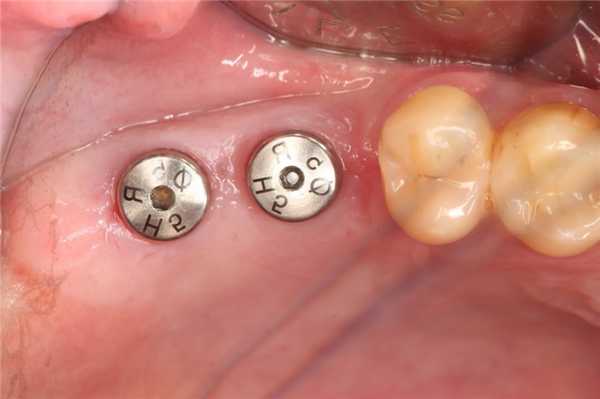

Методика двухэтапной имплантации

Врач проводит разрез десны с отслоением слизистого лоскута. Формируется костное ложе с помощью направляющего канала. Внутрикостный стержень вкручивается вглубь ложа на 0,5-1,0 мм ниже альвеолярного отростка.

После введения стержня, в верхнюю часть вкручивается винт-заглушка для предотвращения врастания тканей в резьбовую часть. Лоскуты слизистой оболочки наглухо зашивают для защиты от попадания бактерий.

Под местной анестезией с помощью зонда определяют место внутрикостного элемента. Десна иссекается до 10 мм и через небольшое отверстие заглушку выкручивают, промывают резьбовой канал. Вкручивается формирователь десны и накладываются швы.

После формирования эстетичного десневого контура (до двух недель) формирователь десны заменяют на абатмент для дальнейшего протезирования.

Имплантация зубов в два этапа

Клинический случай №1

- Хирургический этап имплантации. У пациента был концевой дефект зубного ряда. После прокола десны было установлено два винтовых импланта, наглухо закрыты винтами-заглушками.

- Ортопедический этап. После приживления внутрикостного элемента, был установлен формирователь десны. После успешного формирования десневого края, установили две коронки.